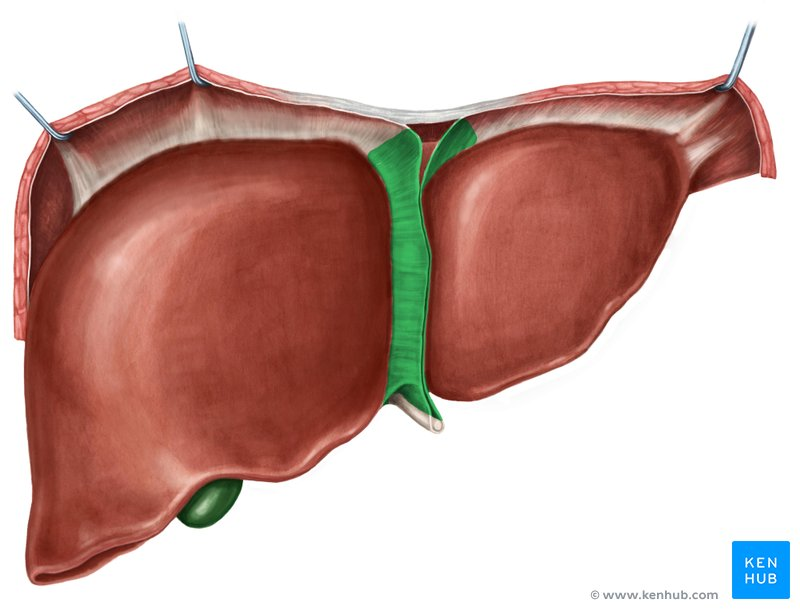

Liver

a large organ located in the upper right abdomen that produces bile, detoxifies blood, and performs many other metabolic functions.

Considered as the largest gland in the body

Right lobe of Liver

The larger of the two main lobes of the liver, located on the right side of the abdomen.

Left lobe of the Liver

The smaller of the two main lobes of the liver, located on the left side of the abdomen.

Quadrate Lobe

A small, quadrilateral lobe of the liver located inferiorly and medially on the visceral surface, bordered by the gallbladder and the fissure for the round ligament.

Caudate Lobe

A small lobe of the liver located posteriorly on the visceral surface, near the inferior vena cava and the fissure for the ligamentum venosum.

Falciform Ligament of the Liver

A broad, thin fold of peritoneum that attaches the liver to the anterior abdominal wall and diaphragm. It also marks the division between the right and left lobes on the anterior surface.

Round Ligament of the Liver

A fibrous cord that represents the remnant of the umbilical vein of the fetus. It is located in the free edge of the falciform ligament.

Gallbladder